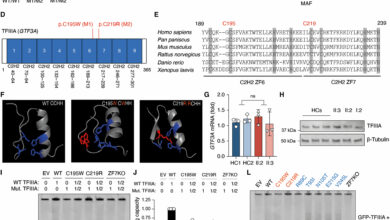

A new therapeutic target for the prevention of heart failure due to aortic stenosis

Cardiomyocyte-specific human β3AR overexpression prevents cardiomyocyte hypertrophy upon catecholamine challenge via NO/cGMP pathway. A Genetic constructs for adeno-associated virus (AAV)…